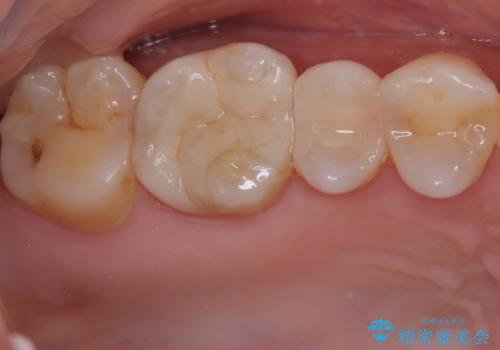

まず、欠けていた詰め物と、その下に存在していた虫歯をすべて丁寧に除去しました。その後、適合性・耐久性・審美性に優れたセラミックインレーを用いて修復処置を行いました。

今回のように、奥歯の詰め物の欠けはご自身では気づきにくいケースも多くあります。違和感がなくても、内部で虫歯が進行していることも少なくありません。